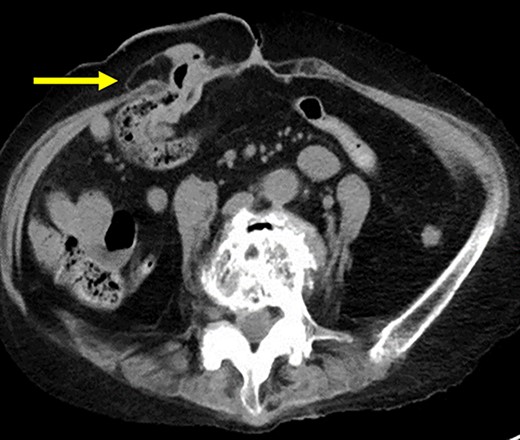

The patient was placed in the supine position. Three ports were used: two 5-mm ports and a 12-mm port placed vertically in the left abdominal (Fig. 2). Adhesions were found around the stoma, and the hernial orifice was exposed while paying attention to damage to the transverse colon and mesentery. Intestinal blood flow was evaluated using intraoperative indocyanine green fluorescent imaging to ensure no damage to the intestinal tract or mesentery (Fig. 3). The hernia defect was closed with one Surgipro™ and 3–0 Vloc™ suture (Fig. 4). The Symbotex Composite Mesh™ 30 × 20 cm was cut into 20 × 20-cm pieces, and the remaining 10 × 10 cm part was turned over and adjusted so that the collagen film touched the transverse colon. The corners of the mesh were fixed with 3-0 nylon for traction, and the folds with collagen film were fixed with 3-0 VICRYL™ (Fig. 5). The mesh was placed in the abdominal space and fixed using an absorbable Tack™ (Fig. 6). The patient was transferred to the Department of Internal Medicine on post-operative day 10 without any post-operative complications. There was no recurrence 6 months after surgery (Fig. 7).

CT scan revealed no recurrence of the transverse colon on the oral side (arrow).